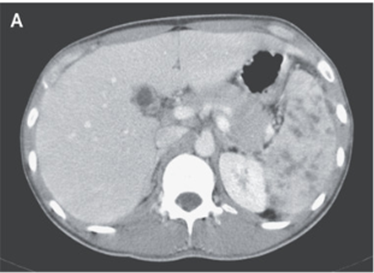

腹部CTでは脾臓に多数の低吸収領域を伴う肥大した脾臓が示された。